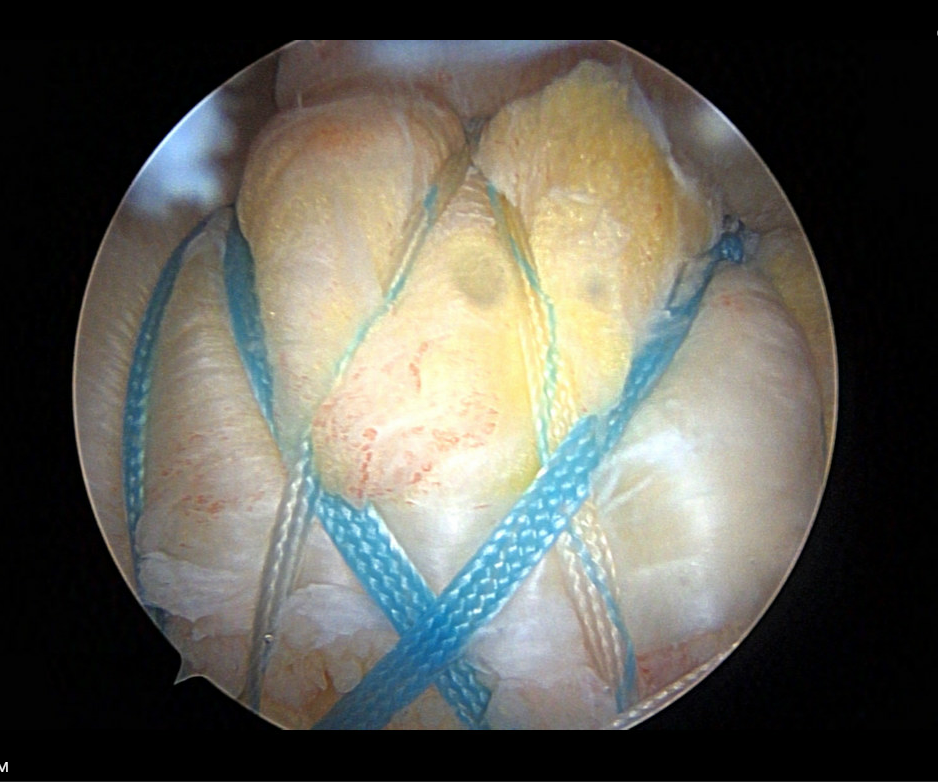

Rotator Cuff Repair

In a typical shoulder arthroscopy procedure, Dr. Cirino may perform several different types of repairs, depending on the diagnosis. Rotator cuff repair is one of the most common procedures performed arthroscopically. Dr. Cirino reattaches the torn tendon to the bone using suture anchors, which are small devices that hold the tendon in place during the healing process. Any bone spurs that may have caused or contributed to the tendon tear are debrided. The long head of the biceps tendon, located beneath the rotator cuff, is often repaired as part of the procedure.